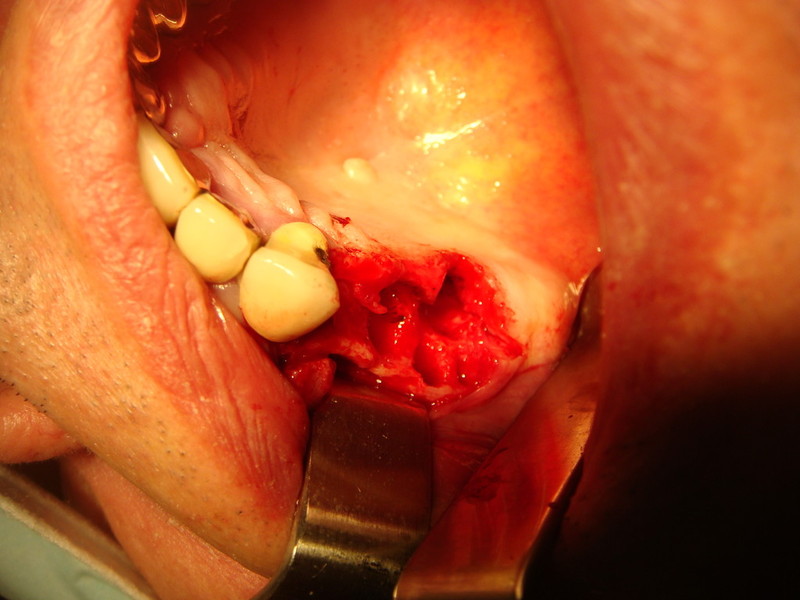

Implantologia avanzata con contestuale rimozione impianti e cisti

Video di una Parte dell'intervento in cui si puo' vedere la comunicazione tra impianti rimossi e pavimento nasale.